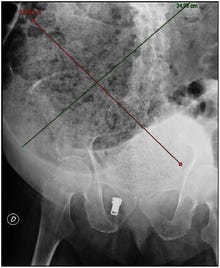

*When I worked in emergency rooms, I occasionally saw severely constipated people. This is an abdominal X-ray of one from Wiki:

Plain abdominal X-ray showing a large fecal impaction extending from the pelvis upwards to the left subphrenic space and from the left towards the right flank, measuring over 40 cm in length and 33 cm in width.